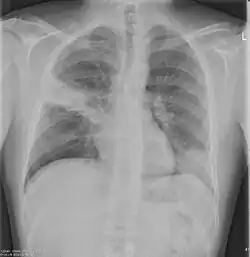

Chest X-rays of a CAP patient before (left) and after treatment

CAP is treated with an antibiotic that kills the infecting microorganism; treatment also aims at managing complications. If the causative microorganism is unidentified, which is often the case, the laboratory identifies the most effective antibiotic; this may take several days.

Chest X-rays and X-ray computed tomography (CT) can reveal areas of opacity (seen as white), indicating consolidation.[14] CAP does not always appear on x-rays, sometimes because the disease is in its initial stages or involves a part of the lung not clearly visible on x-ray. In some cases, chest CT can reveal pneumonia not seen on x-rays. However, congestive heart failure or other types of lung damage can mimic CAP on x-ray.[16]

Ceftriaxone and azithromycin are often used to treat community-acquired pneumonia, which usually presents with a few days of cough, fever, and shortness of breath. Chest x-ray typically reveals a lobar infiltrate (rather than diffuse).[20]